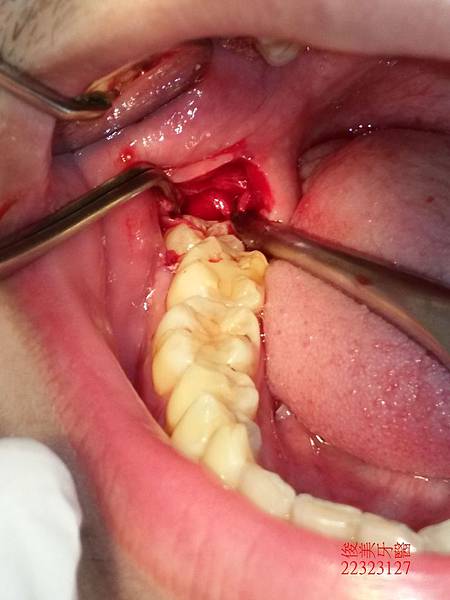

牙齒大且牙根因彎曲抓地力強,需要經驗熟且豐富的醫師來處理。

雖然費了一點時間,但我們還是順利將其全部取出。

術後需強力冰敷3天,注意傷口清潔,等待拆線及傷口復原。